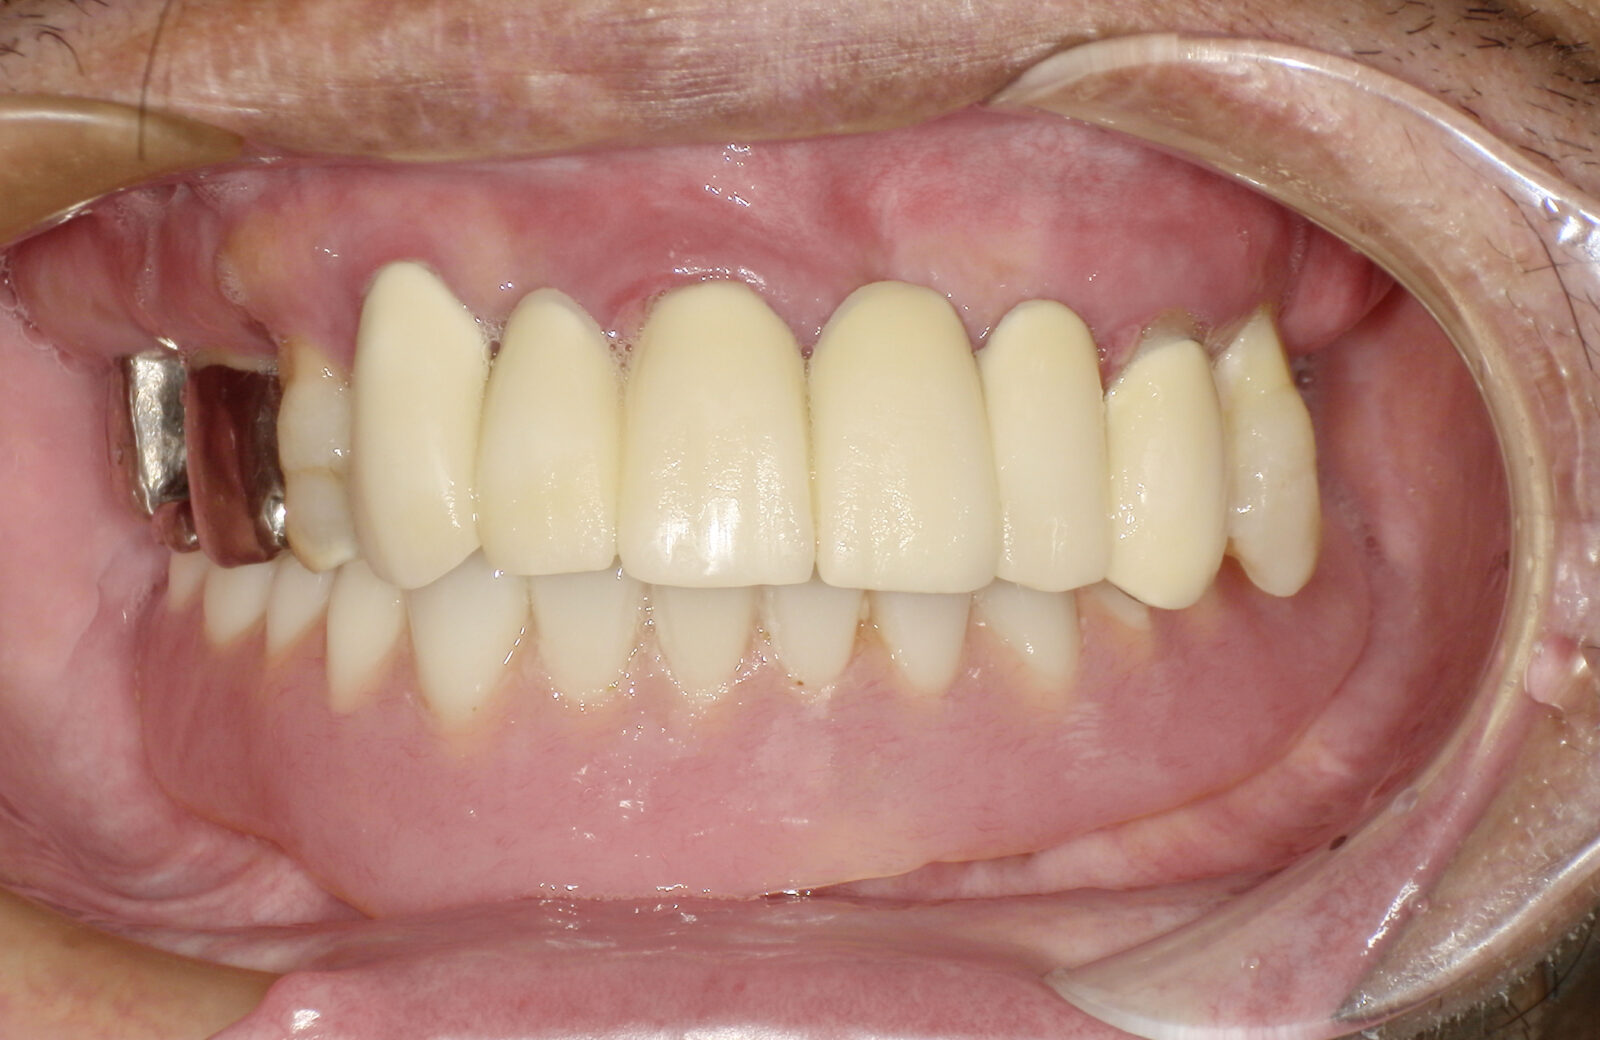

• 治療前

• 治療後

ボロボロの歯を「総合歯科治療」で ※保険外※

ボロボロの状態の治療は「包括的かつ総合的な治療」が必要となります。そのため当院では保険外で治療を行います。

多くの方が、重度のむし歯や歯周病で、抜けてしまっている歯もあるため、まずは虫歯や歯周病治療を行い、残せる歯はしっかり残したうえで、欠損部分の治療を行います。欠損部分に関しては、インプラント、ブリッジ、入れ歯、ケースによってはオールオン4という治療の中から治療法を決定します。